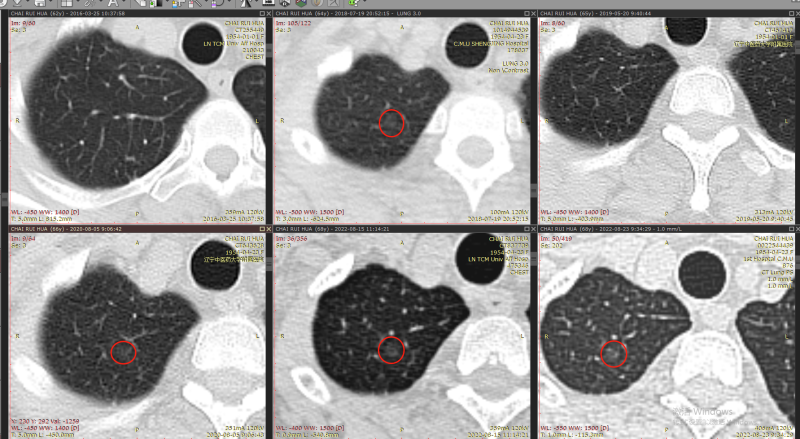

结节1:

2016年-2022年

右肺下叶背段纯磨玻璃结节,最大截面约0.9cm×0.9cm,平均CT值约-431Hu,结节呈类圆形,其中可见小空泡,病灶边界清楚,与9年前CT片比较,病灶密度、大小均无明显变化,考虑为微浸润性腺癌-浸润性腺癌,以微浸润性腺癌可能性大。

问题2:这个结节还能不能继续随访?

答:类似磨玻璃结节继续随访的证据也是有的,指南明确提出首次发现8mm以上的肺结节,按照3月-6月-9月-12月随访,如果病灶发生变化可建议手术,但是这个病灶9年没有变化,说明这个病灶属于惰性生长。前9年没有发生变化,未来9年不发生变化的可能性也是有的。指南也有明确指出等病灶发生变化再去手术。